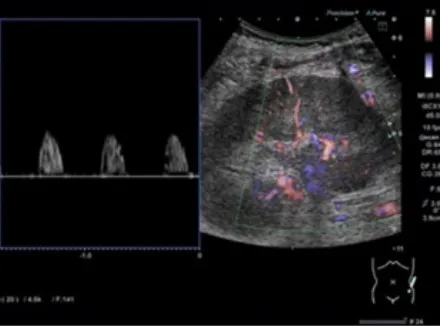

Hematuria e perda rápida da função renal em pacientes com câncer devem levantar suspeita de trombose da veia renal, mesmo sem contraste. Imagens não contrastadas e Doppler podem ser ferramentas-chave nesse contexto.

Valkercyo Feitosa